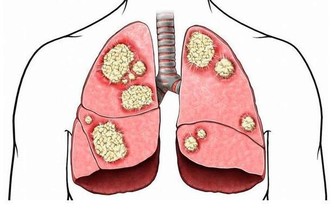

徵兆二:感染次數頻繁

糖尿病會損害免疫系統,讓人們更容易受到感染,當糖尿病患者感染次數頻繁,或者恢復時間越來越長的時候,就應該選擇及時就醫了。